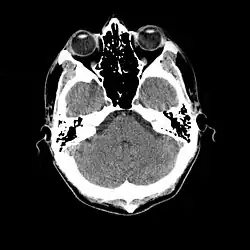

An slice through the head, showing the cerebellum, a small portion of each temporal lobe, the ears, the orbits, and the sinuses. Bone appears white on the black background; brain, eyeballs and ears are grey.

Normal cranial CT scan.

Cranial computed tomography (CT, invented 1972) proved to be an excellent tool for diagnosing cerebral neoplasms in children, including those found in tuberous sclerosis.[46]